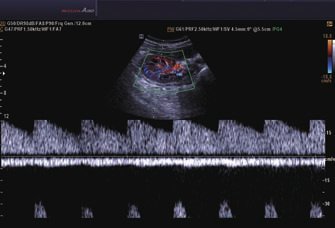

• Farb-Doppler

• Pulsed Wave (PW)-Spektral-Doppler

• Continuous Wave (CW)-Doppler

• Tissue Doppler Imaging (TDI; Gewebe-Doppler-Bildgebung)

• Tissue Doppler Wave (TDW; Gewebe-Doppler-Welle)

• Power-Doppler (PD)

• Directional Power Doppler (DPD)

• Color Opt Flow™ bietet kraftvollere Farben und verbessert die Bildqualität.